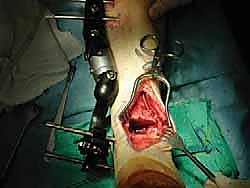

2. الوصول الجراحي (Surgical Approach)

- يستخدم الدكتور هطيف تقنيات الجراحة الميكروسكوبية للوصول إلى المفصل بأقل قدر من التلف للأنسجة المحيطة.

- في بعض الحالات المعقدة، قد يتطلب الأمر إجراء قص عظمي في الكعب (Malleolar Osteotomy) لفتح المفصل بالكامل ورؤية السطح المتضرر بوضوح، ثم يتم إعادة تثبيت هذا العظم لاحقاً.

صور إضافية من داخل غرفة العمليات والخطوات الجراحية

ندرك أهمية توثيق الخطوات الجراحية لطلاب الطب والمرضى الراغبين في فهم دقة الإجراء. هذه الصور توضح مراحل زراعة وتثبيت الطعم العظمي الغضروفي بدقة متناهية تحت إشراف أ.د. محمد هطيف.